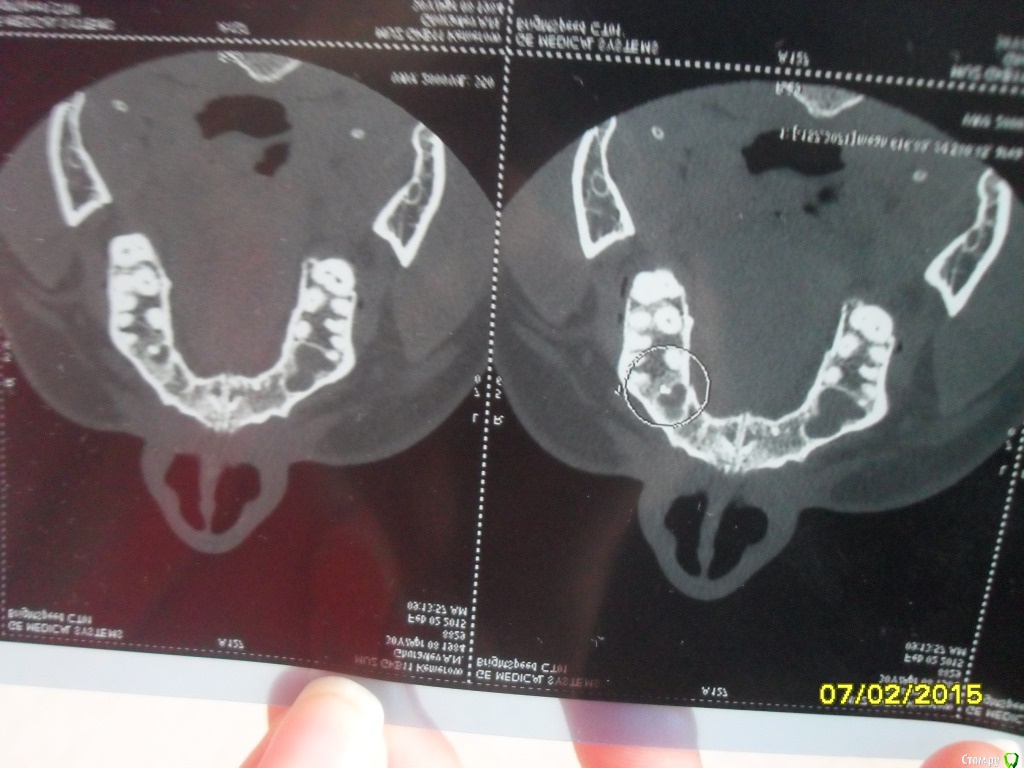

asin Опубликовано 7 февраля, 2015 Поделиться Опубликовано 7 февраля, 2015 (изменено) Добрый день всем, прошу у вас помощи или совета. Ездил на МСКТ пазух носа нашли пломбировочный материал, сломанный инструмент и кисту в правой пазухе 5 зуб. у меня его делали там штифт стоит канал пломбирован((((( мучает хронический катаральный гайморит((((( снимки прилагая может быть подскажите что мне делать.советуют дергать зуб с корнем и потом ушивать потому что откроется вход в пазуху....https://yadi.sk/d/nfWCumo7eU5ST тут образ диска МСКт... если кто то посмотрит буду признателен Изменено 7 февраля, 2015 пользователем asin Ссылка на комментарий

asin Опубликовано 16 февраля, 2015 Автор Поделиться Опубликовано 16 февраля, 2015 (изменено) надо дентальное КТ сделать, тогда будет ясно есть ли шанс перелечить зуб. Ну или сразу удалить.по рекомендации ЧЛХ удален зуб снимок прилагаю. я так понимаю пломб. мат остался.перфорация не нарушена. какую операцию рекомендуете Изменено 16 февраля, 2015 пользователем asin Ссылка на комментарий